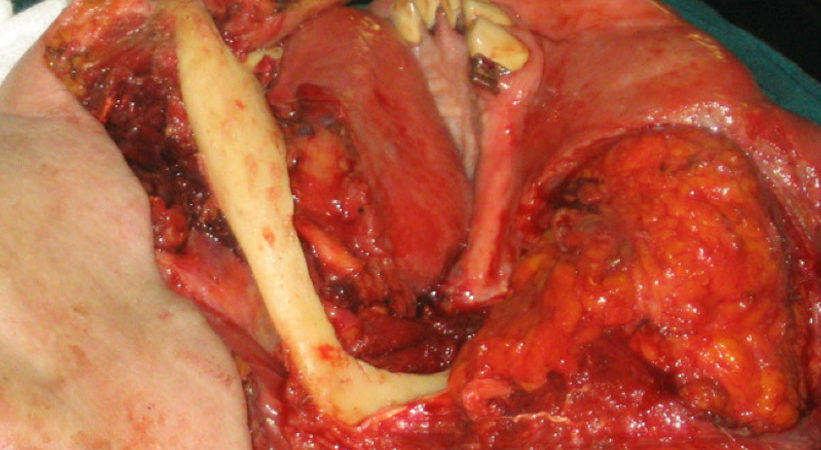

CASO CLINICO N° 3

Paziente di 92 anni portatore di un carcinoma squamoso dell’emipalato duro di sx infiltrante il seno mascellare omolaterale T4N1. È stata effettuata una maxillectomia parziale con dissezione conservativa del collo.

RISULTATI E CONCLUSIONI

Tutti i pazienti operati hanno ben sopportato l’intervento, non si sono verificate nè emorragie nè infezioni post-operatorie e la degenza è stata di breve durata; tutti i pazienti hanno conseguito un buon risultato estetico e funzionale. La chirurgia piezoelettrica infatti causa un trauma minimo sull’osso con scarso sanguinamento permettendo una guarigione più rapida dei tessuti. Riteniamo che questa tecnica in determinati casi selezionati, soprattutto in pazienti di età avanzata, possa costituire una valida alternativa alla chirurgia tradizaionale.